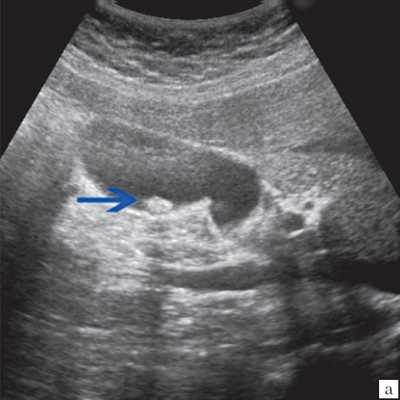

(Левый) Пример неполного кальциноза: у женщины 67 лет, жалующейся на боли в правом верхнем квадранте живота после еды определяются отдельные гиперэхогенные очаги передней и задней стенок желчного пузыря, отбрасывающие неоднородную тень.

(Правый) Пример неполного кальциноза: у мужчины 61 года в стенке желчного пузыря визуализируются точечные кальцинаты. Выявленные при патологоанатомическом исследовании конкременты не визуализируются.